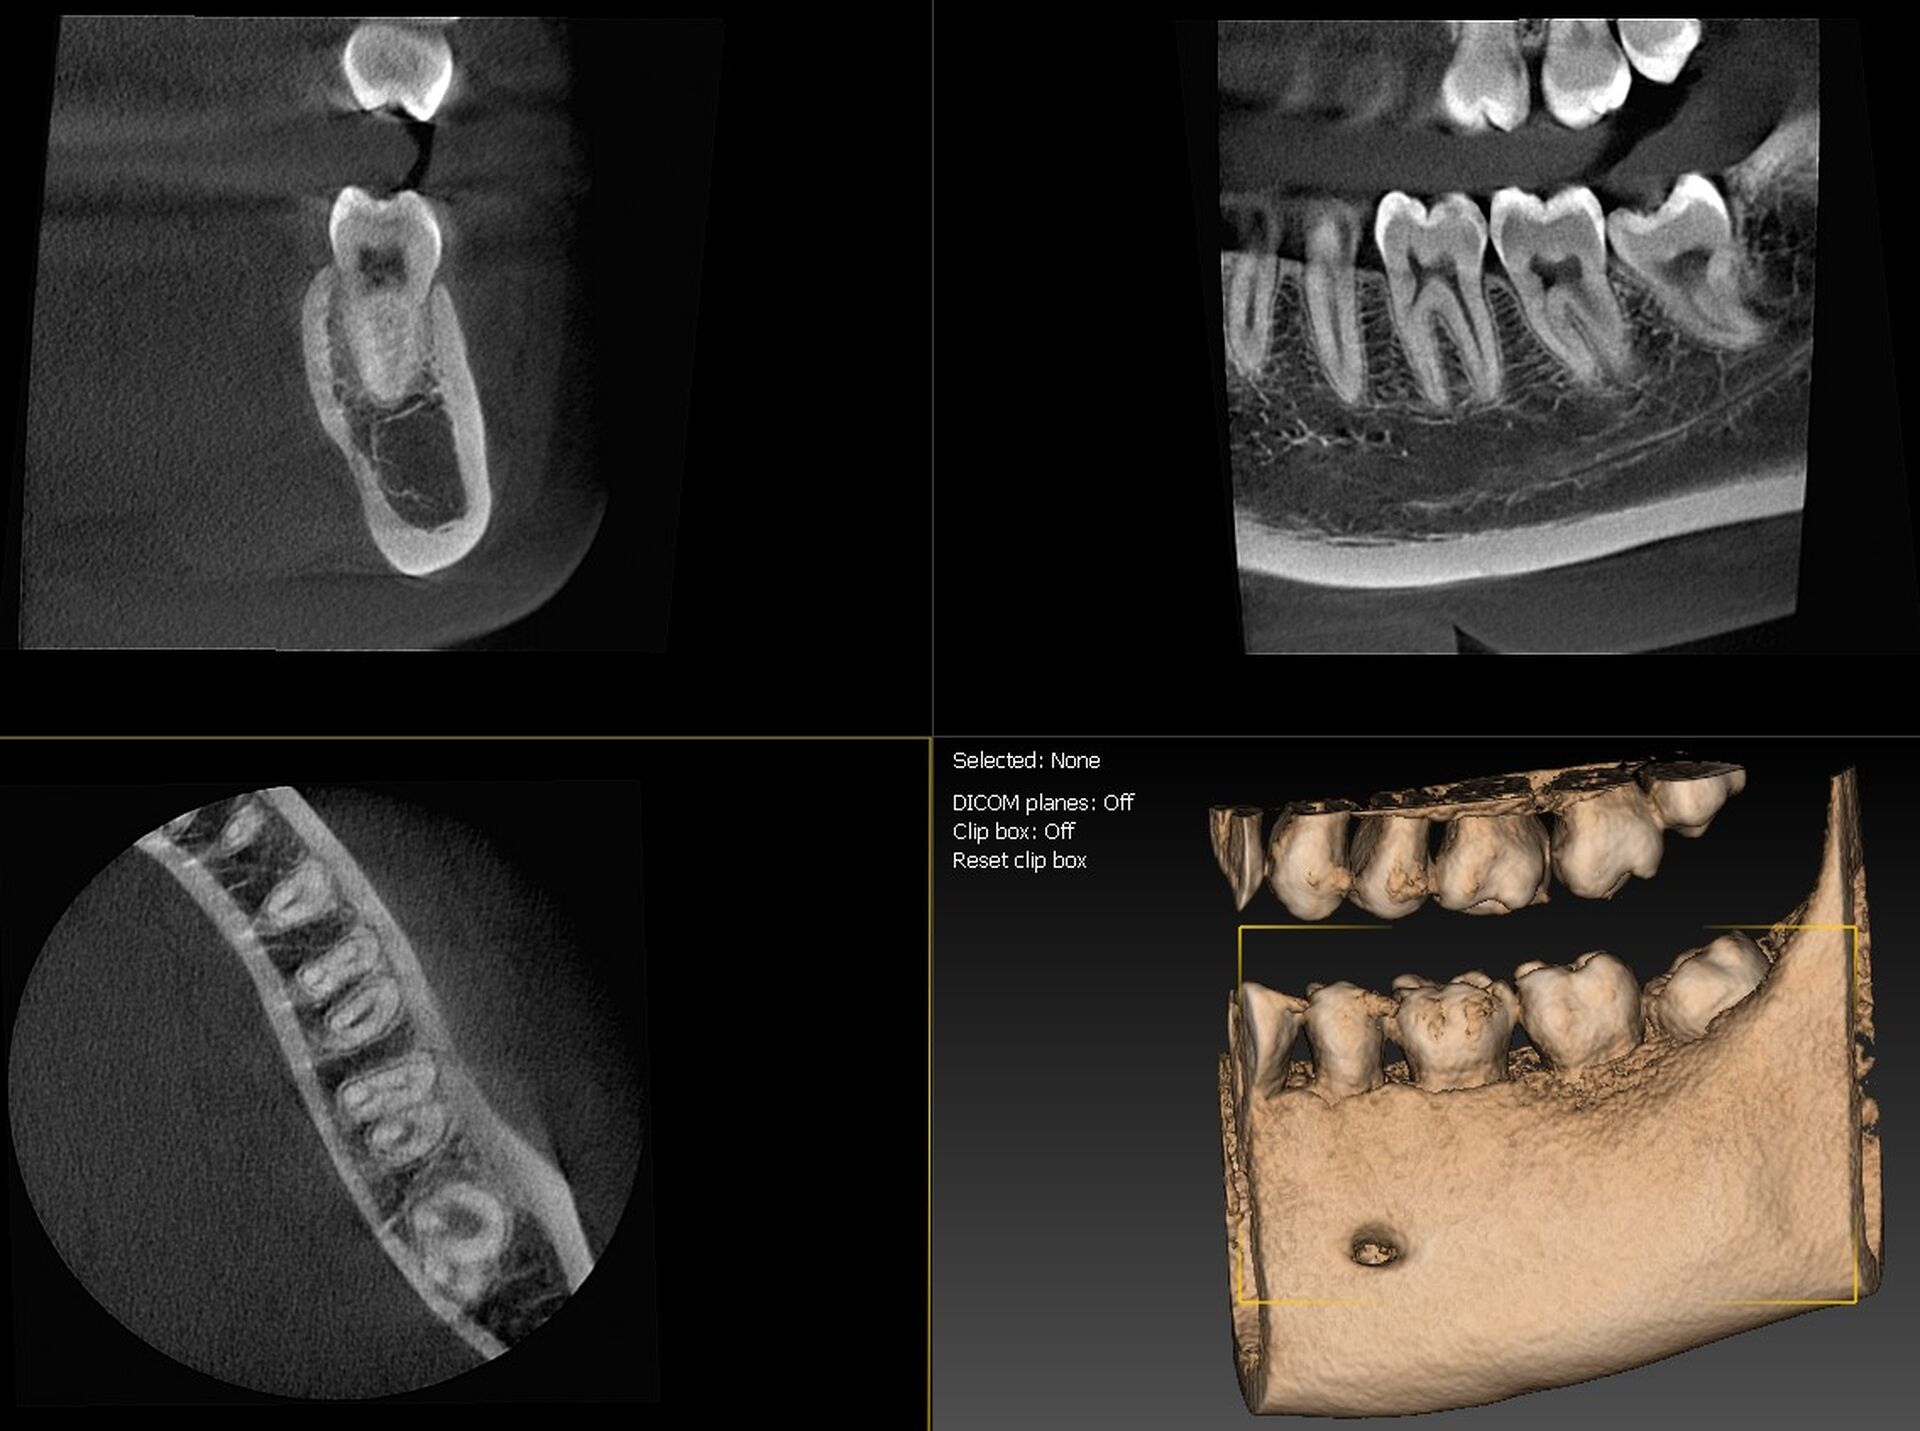

L’I-Max 3D XPRO est un système Cone Beam multifonction 4-en-1 conçu pour fournir une imagerie dentaire ultra-précise dans divers modes : panoramique, 3D, céphalométrie et scan d’objets (modèles en plâtre, porte-empreintes).

La qualité d’image est exceptionnelle, avec une résolution de 70 microns, assurant une finesse diagnostique accrue.

Le champ d’imagerie (FOV) peut être ajusté entre 16×11 cm à 5×5 cm, ce qui permet de cibler précisément la zone d’intérêt et de limiter l’exposition aux rayonnements.

La technologie Super IGZO est au cœur de ce système, avec des innovations telles que le traitement IA (algorithmes de débruitage), le Focus Scintillator pour réduire le bruit et l’algorithme AutoMAR pour atténuer les artéfacts métalliques.  Le positionnement "face à face" améliore le confort du patient et la reproductibilité des prises de vue.

Grâce à sa compacité (empreinte au sol inférieure à 1 m²) et son installation murale ou en colonne, l’appareil peut s’adapter aux contraintes d’espace des cabinets.  L’interface est intuitive, facilitant le passage entre les modes 2D et 3D, et la planification implantaire est supportée par le logiciel QuickVision 3D intégré pour visualiser, simuler et guider les interventions.

En résumé, l’I-Max 3D XPRO combine haute résolution, polyvalence, algorithmes de traitement intelligents et adaptabilité pour optimiser le diagnostic, la planification chirurgicale et l’efficacité clinique au sein des cabinets dentaires modernes.